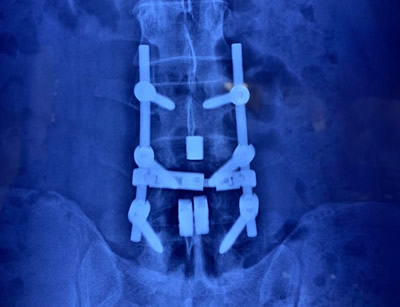

GALLERY

Images gallery